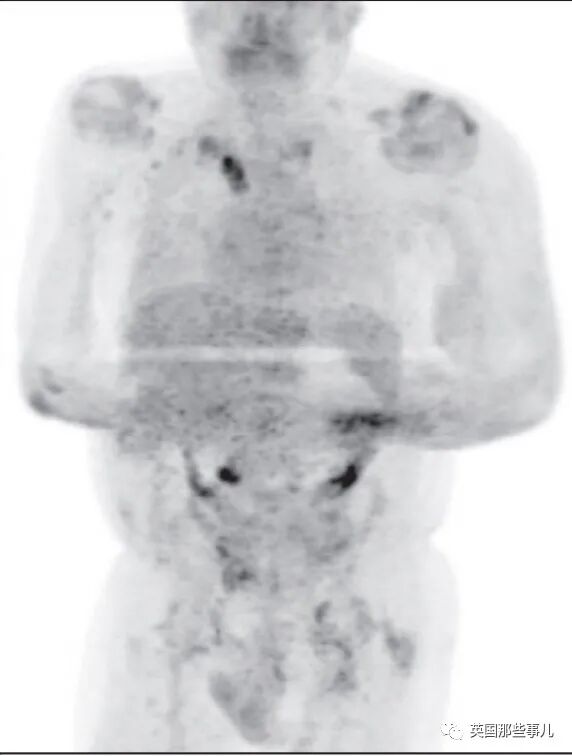

在家里康复了4个月后,这名患者到医院复查,CT检查的结果让医生大吃一惊:

肿瘤相关的生物标志物水平也下降了90%以上,就连患者颈部的淋巴结肿块也缩小了N倍。

癌细胞被大量清除后

反复检查多次后,医生们最终确认:

在感染新冠病毒,又自我康复4个月后,这位61岁患者身体里的癌症竟然奇迹般地痊愈了!